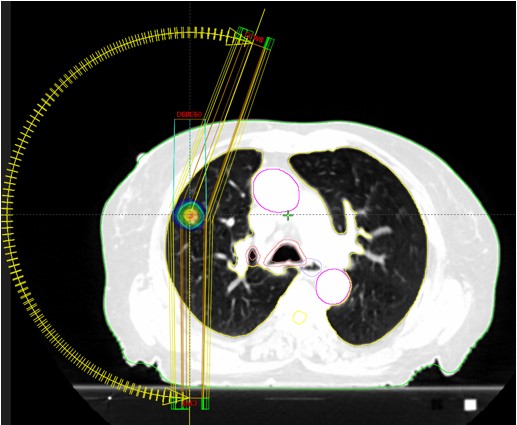

Bolesnica, rođena 1942.

Dijagnoza:

Npl pulmonis lateris dextri (2020)

SABR npl pulmonis lat dex (11/2020)

Meta pulmonis

SABR meta pulmonis (7/2023)

Rezultat – 33 mjeseca nakon RK

Potpuni nestanak tretirane lezije